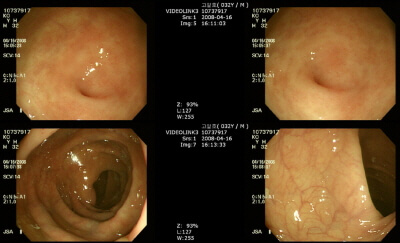

대장암을 확인하기 위해서는 대장내시경 또는 분변잠혈검사를 하는데요. 국내 연구진이 한두방울의 혈액으로 대장암을 진단할 수 있는 기술을 개발하여 상용화한다고 합니다.

한국 기초과학 지원 연구원이 혈액을 한두 방울 떨어뜨리면 대장암을 진단할 수 있는 기술을 개발하였다고 합니다.

연구진이 개발한 바이오센서가 대장암 환자의 혈액에 있는 대장암표지자와 만나면 색이 변하는데 전기로 신호를 증폭시켜 진단하는 방식으로 기존의 혈액 분석 방법과 비교해 민감도가 10배 이상 높고 초기 대장암도 선별할 수 있다고 합니다.